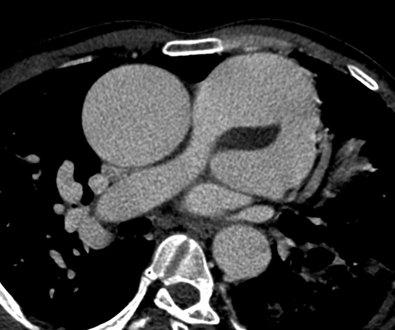

Persistent truncus arteriosus is an uncommon complex congenital heart disease. Without surgical intervention, the prognosis is not good. Very few untreated cases of truncus arteriosus survive to maturity. We report an exceptional case of uncorrected truncus arteriosus surviving into adulthood of type a3 variant -van praagh classification as a 26-year-old male who had well tolerated dyspnea since birth. Our patient showed a single(right) pulmonary artery arising from the common arterial trunk supplying the right lung and absent main and left pulmonary artery with collateral supply to the left lung consistent with the truncus arteriosus type a3-van praagh classification